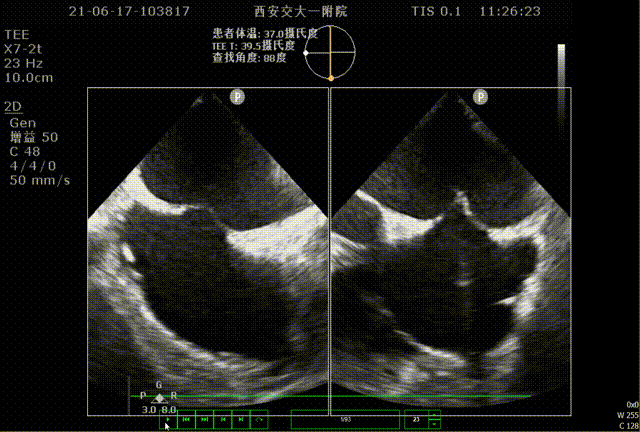

86°TEE

该患者左心耳开口较小,呈反鸡翅型,开口处即反折,同时内部梳状肌发达,且深度较浅,因此手术难度偏大,术前安排进一步CT评估以协助制定手术策略。

RAO30° CAU25°造影,左心耳形态充分暴露,可以观察到心耳属于反鸡翅形状。内部梳状肌较发达,深度较浅。

DSA测量开口17mm,深度19mm,与CT测量结果类似,考虑选择24mm watchman封堵器,首选X3轴向进行封堵。